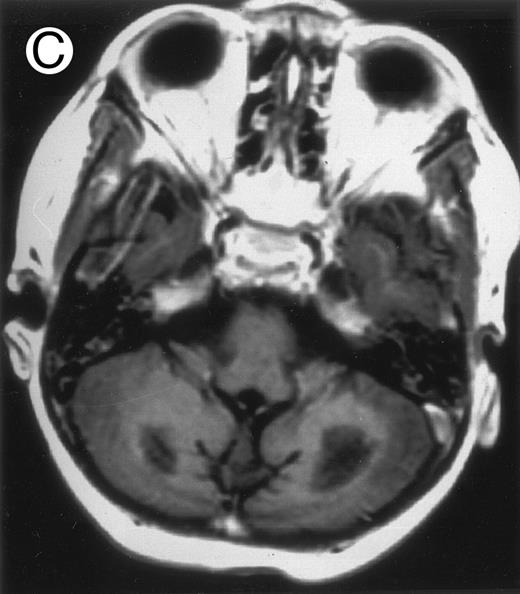

Three different aspects of brain imaging in HLH patients. (A) CT scan of a 3-month-old baby showing a large subdural effusion, several necrotic areas and hypodensities of the white matter. (B) Brain magnetic resonance of a 14-month-old boy showing large confluent areas of hypersignal in T2-weighted images. (C) Large symmetrical necrotic areas of cerebellar white matter in a 41/2-year-old girl (MRI).

Among the nine children with initial neurological symptoms, seizures were the most frequent initial symptom in the youngest patients, whereas ataxia was found in the two oldest patients (46 and 58 months old, respectively) (Table 1). All nine patients had the same CSF abnormalities as patients with meningitis only. Eight of these nine patients had a neuroradiological study performed at the time of their first neurological symptoms (Table 1). The two most frequent lesions were focal necrosis with parenchymal volume loss and atrophy (Fig 2A and C) and white matter abnormalities (Fig 2B). Several small focal lesions with hypersignal at MR imaging that enhanced after administration of gadopentate dimeglumine (or contrast on CT scan) were also observed in two cases.

Together, 19 patients had primary severe CNS disease progression or CNS relapse (Fig 1). Three of 19 had a CNS relapse characterized by meningitis only. Neurological symptoms occurred in 16 of these 19 patients (9 from the onset and 7 after the initial meningitis) (Fig 1). No clinical or neuroradiological difference was detected between the patients who developed neurological symptoms as the initial CNS manifestation or after initial meningitis (Table 1). The occurrence of these neurological manifestations marked a turning point in the evolution of the disease, as chemotherapy led to an improvement of the neurological symptoms in only three patients despite the use of intensive treatment by MTX IT. In these three patients, neurological sequelae persisted after the first symptoms and a relapse occurred within 3 to 10 months. Brain imaging was repeated during chemotherapy for four patients with progression of the CNS disease: in three patients, a severe brain atrophy developed (Fig 3A and B) and in the last patient who initially had contrast enhancement in cerebellar white matter, a cerebellum parenchymal loss was observed (Fig 2C). All of these 19 patients treated by chemotherapy only (n = 15) died during a last episode of coma and brain stem symptoms associated with a systemic hemophagocytic syndrome, 6 ± 6 months after the first neurological symptom (irrespective of the age at this first event). Four of these 19 patients were transplanted (one patient received an HLA-identical BMT, three an HLA-partially identical BMT). Median delay between diagnosis and BMT was 14 months (range, 2 to 20 months). All of these four patients died of BMT-related toxicity and/or disease progression.